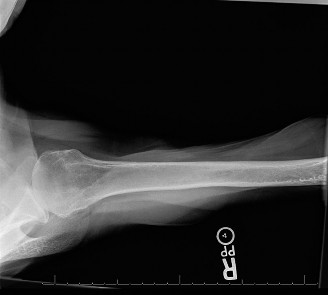

The correct answer is (E). Given that her rotator cuff has atrophied and has fatty infiltration to the point where there are equal parts fat and muscle, this is considered an irreparable rotator cuff tear. Repair should not be attempted because of poor outcomes following repair (see last two paragraphs of this discussion below). A reverse total shoulder arthroplasty is an alternative to repair that should be used in cases of massive, irreparable rotator cuff tears. It is a semi-constrained prosthesis that restores function in patients with massive rotator cuff tears by constraining a concave humeral cap inferior to a semispherical glenoid component (glenosphere). This creates an inferior force-couple and a fulcrum that replaces the stabilizing function of the infraspinatus maintaining a center of rotation around which the shoulder can move. This allows the deltoid to abduct and flex the shoulder without causing the humerus to migrate superiorly and about the acromion. In an elderly patient with a massive, irreparable rotator cuff tear (as in this patient), a reverse total shoulder arthroplasty is the procedure of choice.

It should be noted that reverse total shoulder arthroplasty is also the procedure of choice in patients with cuff-tear arthropathy (aka rotator cuff arthropathy). Characteristics of cuff-tear arthropathy include superior migration of the humerus due to a massive rotator cuff tear, glenohumeral joint destruction, subchondral osteoporosis, and humeral head collapse (see Fig. 2–17). A reverse total shoulder

arthroplasty in this case serves the purpose of eliminating pain caused by glenohumeral joint arthritis while restoring functional motion and is the procedure of choice in patients with cuff-tear arthropathy.

Figure 2–17_X-rays of a patient showing evidence of cuff tear arthropathy. The humerus is migrated superiorly, the glenohumeral joint is destroyed, there is subchondral osteoporosis, and the humeral head is collapsed. (From Ecklund KJ, Lee TQ, Tibone J, Gupta R. Rotator cuff tear arthropathy. _J Am Acad Orthop Surg. 2007;15(6):340–349.)